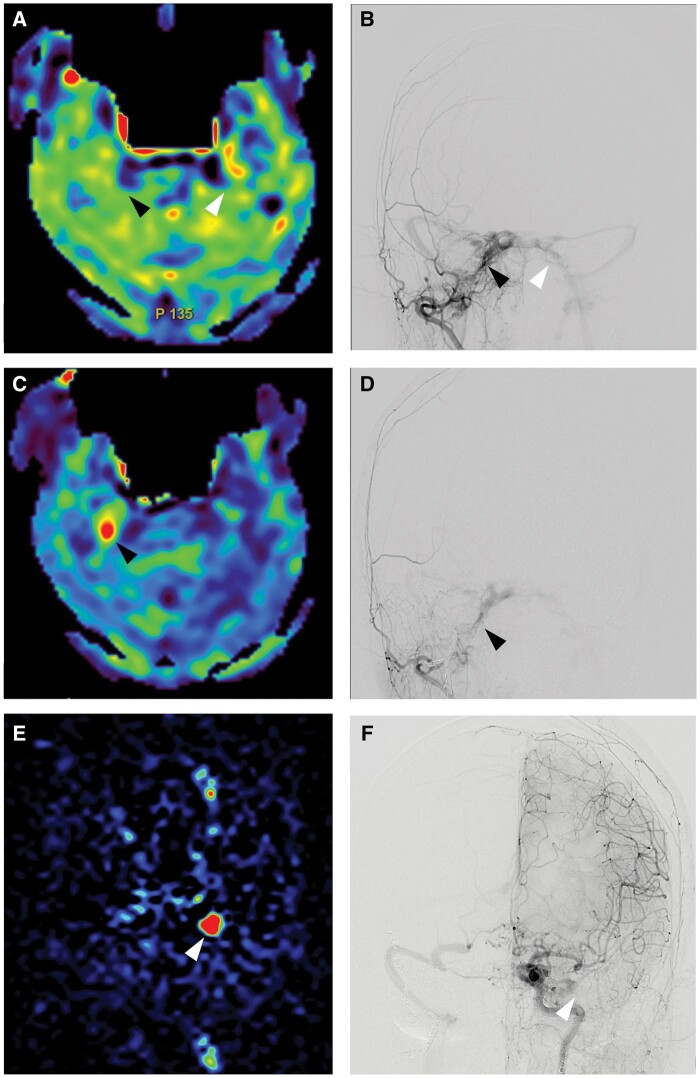

Several reports indicate that arterial spin labelling (ASL) MRI is useful for the diagnosis, identification of cortical venous reflux, and assessment of therapeutic effect in dural arteriovenous fistula (dAVF). However, there is no reports indicating the utility of ASL in the identification of venous sinus obstruction. We herein report the case of a 72-year-old woman who presented with diplopia and right trigeminal neuralgia due to bilateral cavernous sinus dAVF. Digital subtraction angiography (DSA) showed temporal occlusion of the inferior petrosal sinus (IPS) and ASL indicated hyperintense signal in the IPS. The ASL signal could indicate venous stasis soon after the occlusion based on the serial changes of IPS patency and occlusion observed in the DSA.